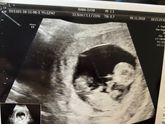

В понедельник пойду узнавать пол??❤️ очень волнительно! Интересно, на моем сроке возможно определить)?

7 декабря 2018 05:27